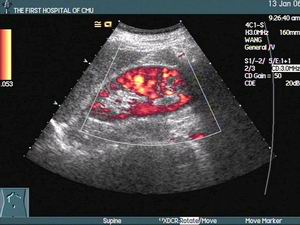

3.心肌閃爍圖及一些現代輔助檢查診斷對妊娠心肌梗死的診斷均有幫助。

妊娠性心肌梗死原理圖 2.與妊娠中出現某些臨床症狀及體徵的鑑別當妊娠期孕婦出現頸靜脈怒張、出汗、面色蒼白、四肢濕冷,或伴發其他症狀,如心動過緩、低血壓、心律失常時,特別是伴有胸痛的患者,應該想到本病的可能。此時需要與某些心臟病引起的心衰及其他合併症相鑑別。